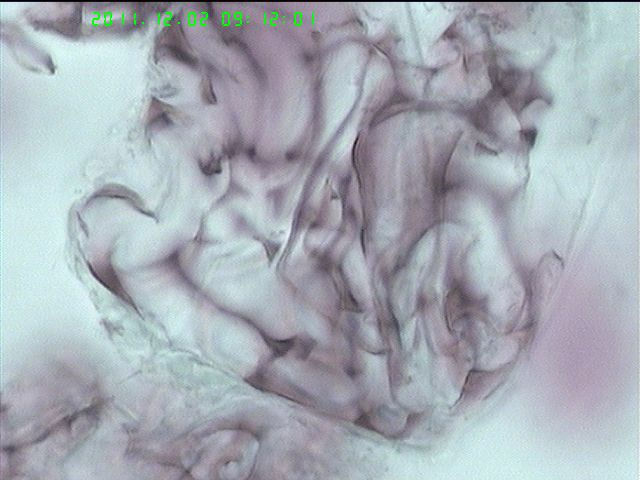

肺泡灌洗液

粘液性物。

粘液性物或霉菌

细支气管粘膜脱落后发生退变

大概也许可能差不多是浓稠粘液。